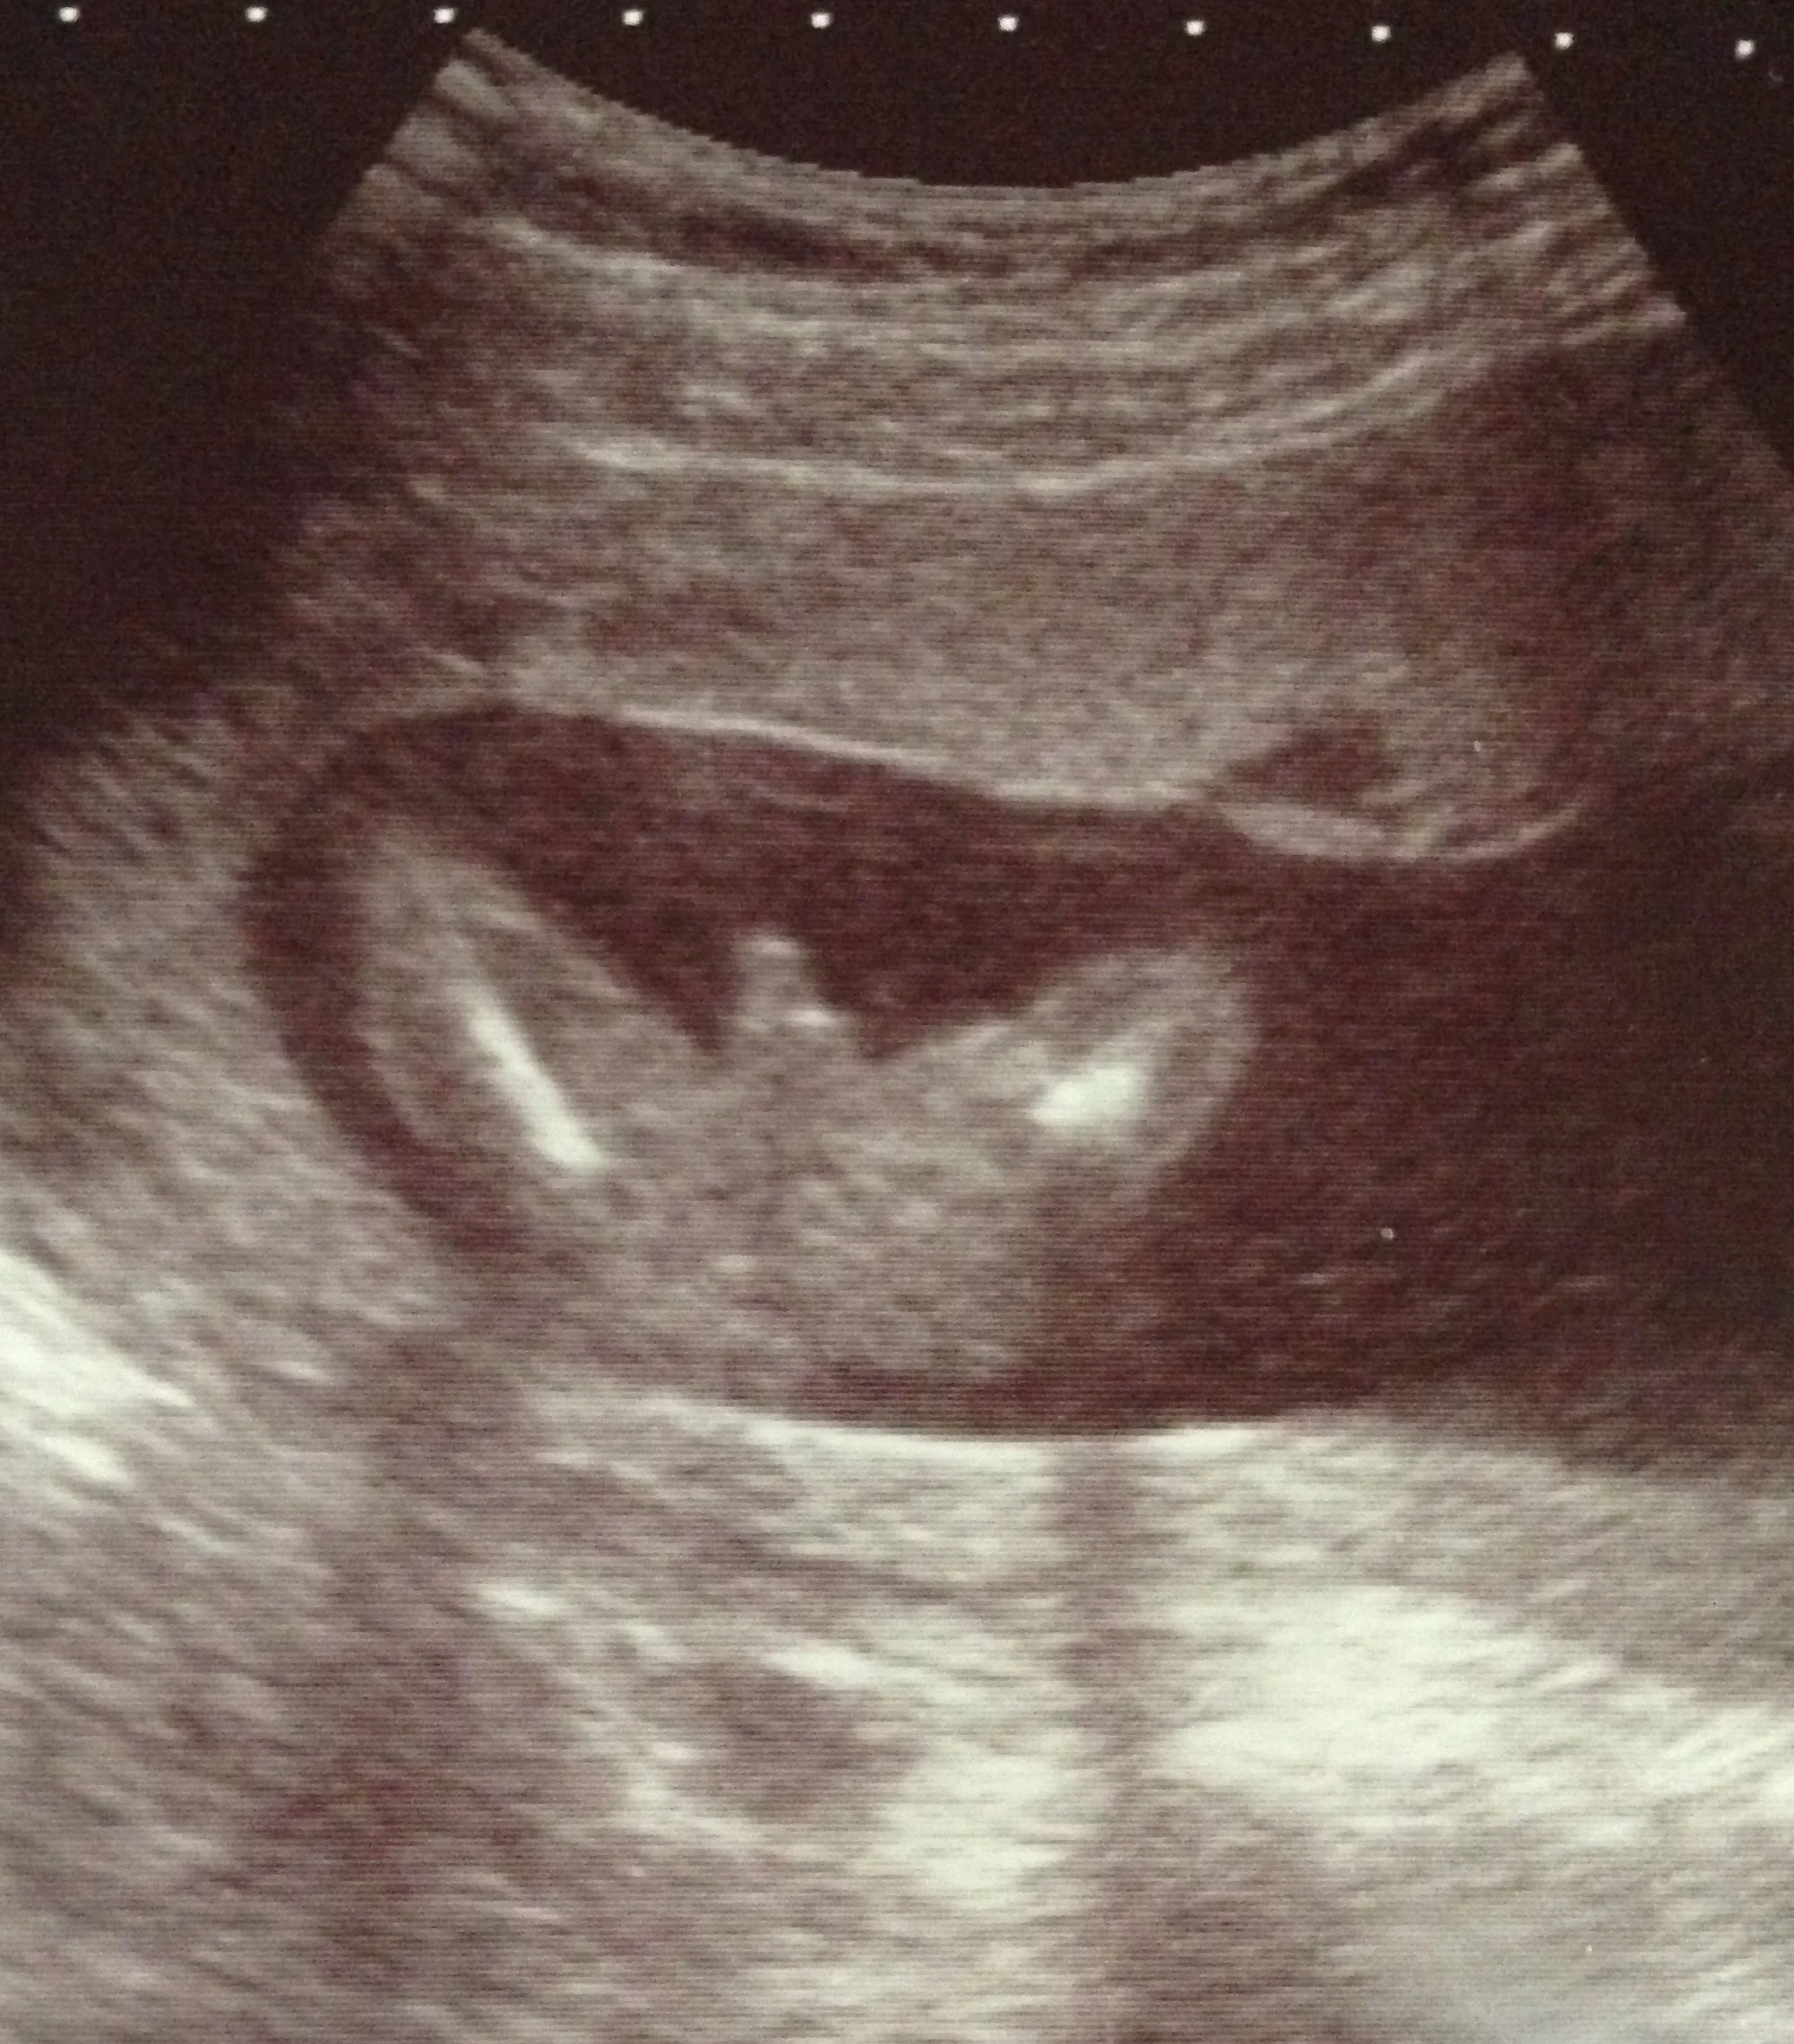

IT was very clear that i was pregnant with a boy,...